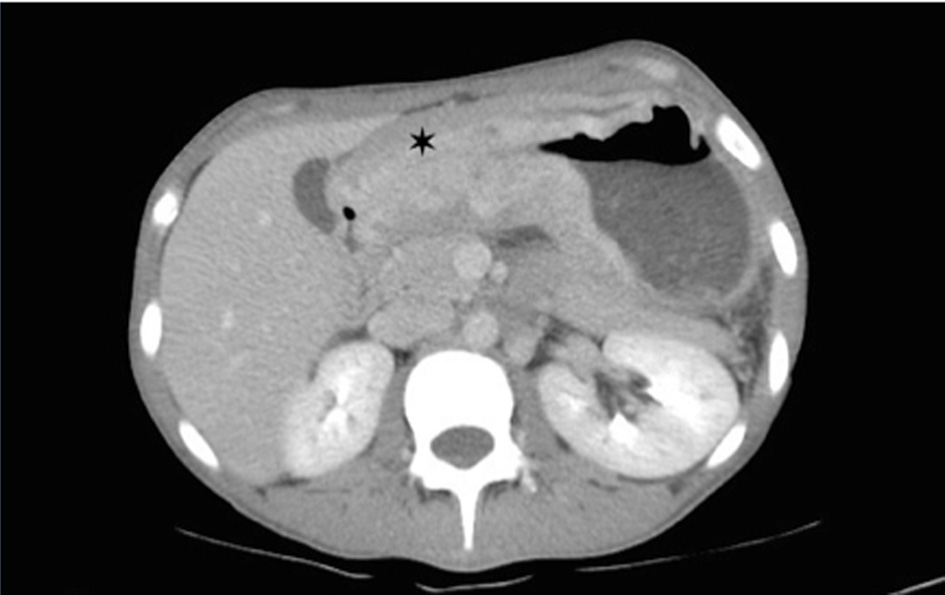

Corticosteroids were prescribed for fetal lung maturity and investigation started for wasting syndrome. In upper GI endoscopy a tumor lesion was observed invading the whole gastric antrum (infiltrative aspect Borrmann IV) not being possible to guide nasogastric tube, biopsies were made and parenteral nutrition started. The histopathological study was compatible with signet ring carcinoma, undifferentiated Nakamura or diffuses Lauren (Fig. 1, 2) negative for HER2 receptor and estrogen receptor. The patient chose to wait until 34 weeks for resolution of pregnancy, abdominal delivery being held without complications and in a second surgical time, laparotomy revealing suggestive peritoneal carcinomatosis, confirmed by histopathology. The baby was a female, weighed 1,400 g and had Apgar 7:8 in the first and fifth min respectively, without mechanical ventilation requirement. Chest and abdomen postoperative CT scans were performed (Fig. 3) where locally advanced disease was observed. The postpartum evolved without surgical complications and was referred to oncology service in order to perform chemotherapy, being initiated scheme with cisplatin and capecitabine, with good tolerance for the patient with a partial response in 4 months after initiation of therapy.

![]() Click for large image | Figure 3. Abdominal tomography with intravenous contrast revealing intense thickening of the gastric wall with diffuse narrowing in the pre-pyloric region (asterisk). |